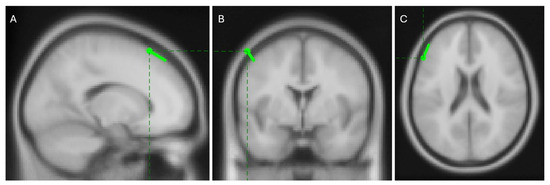

Preliminary data from an 11-year-old right-handed healthy participant performing ‘Task 1′ with his right hand showed promising results. Using the EMG signal as a reference, the RPA algorithm identified distinct EEG sources, as illustrated in Figure 13.

Figure 13.

EEG sources separated by RPA using the EMG signal as reference.

Among these sources, the one with the highest PLV, shown as the left-most map in Figure 13, is expected to represent a clear dipolar source located in the brain cortex contralateral to the movement. Localization with the FieldTrip toolbox places this source in the left caudal middle frontal area, as shown in Figure 14. This region is well-documented for its role in manual control [56,57,58,59,60] and its contralateral location aligns with the known physiology of human motor function [61]. These results support the hypothesis that phase synchrony is a strong candidate for explaining corticomuscular control.

Figure 14.

Sagittal (A), coronal (B), and transversal (C) views of the localization of the most synchronous source situated in the left caudal middle frontal area. Images present standard magnetic resonance slices which are not fixed at the dipole position.